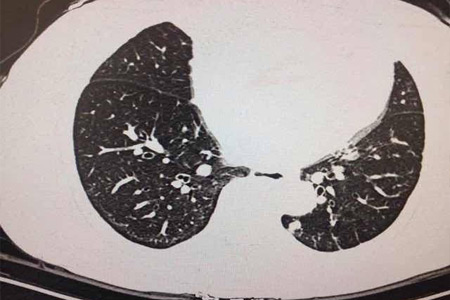

肺癌是一種常見的惡性腫瘤,其發生與多種因素有關,包括遺傳因素。近年來,随着基因檢測技術的發展,人們越來越關注其在預測肺癌患病風險中的作用。